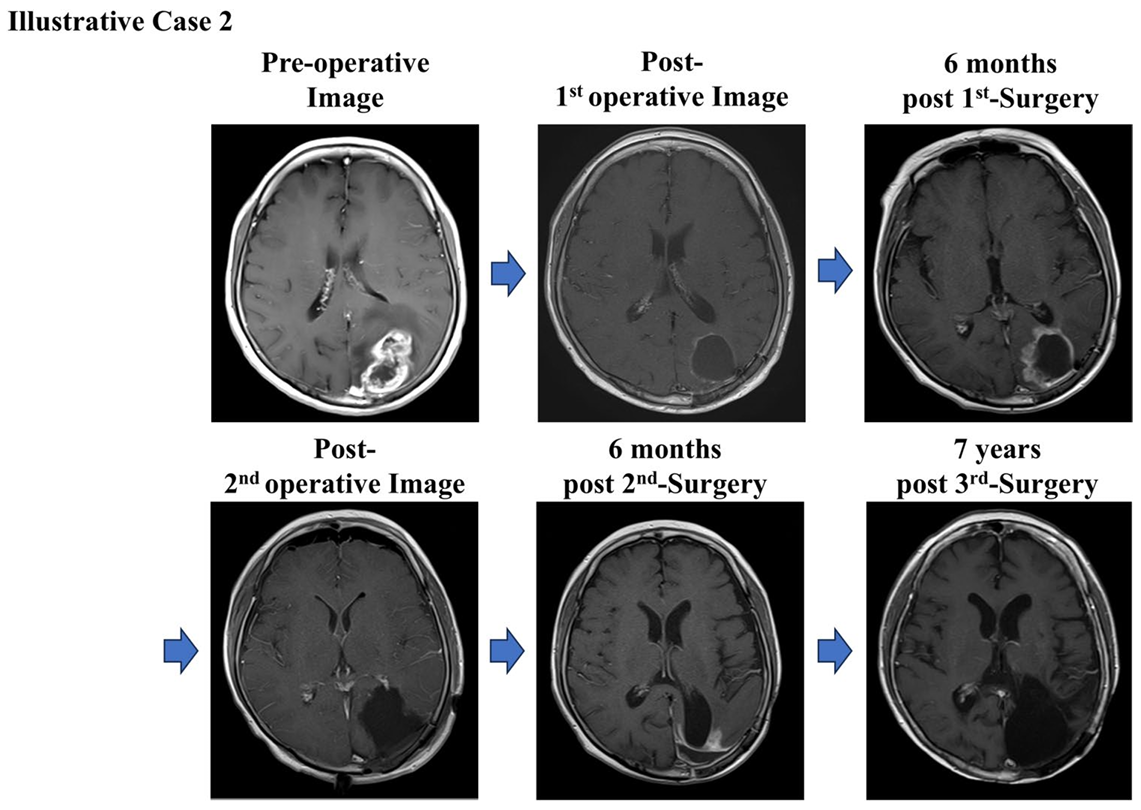

Koriyama et al. (2025) の研究では、62歳の女性患者が対象となった症例が報告されています。

診断と治療経過:

患者さんは進行性の失語症(言語障害)と右半身麻痺(右半身の筋力低下)で受診され、MRI検査では左前頭葉および頭頂葉に複数の造影病変が認められました。

患者さんは腫瘍摘出手術に加え、光線力学療法(PDT)による肉眼的全摘出(Gross Total Resection: GTR)を実施。その後、自家がんワクチン(AFTV)療法を受けました。

出典: Koriyama, S. et al., 2025. Brain Tumor Pathology, 42:76–86, Fig. 2. CC BY 4.0. 詳細はPubMedをご参照ください。

治療結果:

- 術後9年間再発なしで経過観察中

- 言語障害や半身麻痺は残りましたが、Karnofsky Performance Status(KPS)60を維持

- 微小な残存腫瘍に対しても免疫が持続的に働き、長期制御に成功

この症例は、AFTV療法が標準治療では対応が難しい微小残存腫瘍に対しても有効である可能性を示しており、高齢者や再発リスクの高い患者さんにとって新しい希望となり得ます。